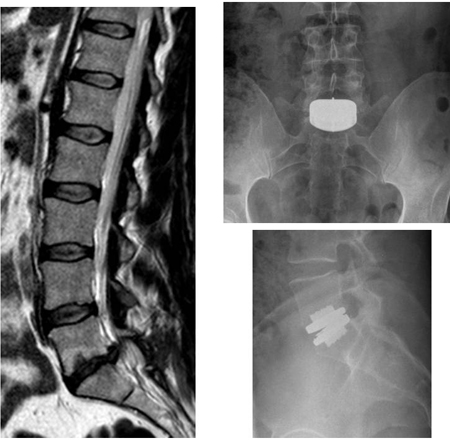

Artificial disc replacement (ADR)

ADR is another surgical technique, not in routine clinical practice, that involves complete removal of the injured or degenerated disc material and replacement by an artificial disc. [Figure caption and citation for the preceding image starts]: Disc replacement: patient presents with severe back pain, having previously undergone right L5S1 discectomy for a right S1 radiculopathy. Though initially recovered, the right S1 pain recurred after 10 months, with back pain. An MRI scan shows a degenerate L5S1 disc (left, T2-weighted sagittal view). Patient subsequently had a disc replacement (AP radiograph top right, lateral bottom right). The pain in the back and the right leg resolved completelyFrom the collection of Dr N. Quiraishi [Citation ends].

The aim of this device is to restore the normal kinematics of the disc, relieving pain while avoiding instability and protecting adjacent facets from undue degeneration. The principle of replacing the entire disc is based on the success of other, similar prostheses designed and used for other joints (knee and hip replacements). Therefore, the materials that have been used are also similar (polyethylene, chrome, cobalt, titanium).

Indications for the use of ADR include: failure of conservative management; and disabling LBP attributed to degenerative disc disease affecting no more than 2 discs.[156]Fekete TF, Porchet F. Overview of disc arthroplasty-past, present and future. Acta Neurochir (Wien). 2010 Mar;152(3):393-404.